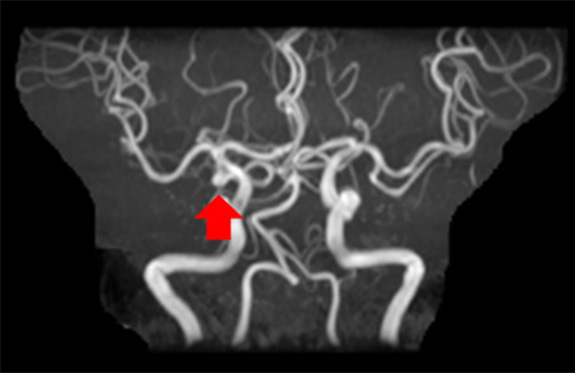

頭の中の動脈の血管です。

横回転で12方向、縦回転で12方向の計24方向の頭部動脈の写真を作りいろいろな角度から観察します。この写真は横回転、縦回転の中の一枚ずつの写真です。

この画像で血管の途中が狭くなっていたり無くなっていないかを見たり、未破裂動脈瘤と言って血管にコブみたいなものが出来ていないか確認することができます。

未破裂動脈瘤(頭部血管)